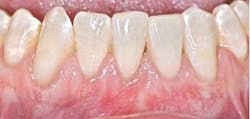

Depending on the severity and extent that the mucogingival defects present, we often administer a hybrid/combination therapy. Many of our patients previously experienced mucogingival grafting procedures at other offices, searched the Internet, or discussed with friends who have had soft-tissue grafts, and as a result they are extremely fearful of the dreadful “pizza burn” that one may experience after harvesting from the palate. As reported in the literature and confirmed clinically in our office, with the addition of an enamel matrix protein, patients consistently report minimal postoperative swelling and discomfort. This has been a huge game changer for our practice and will be for yours too (figure 3). (7)